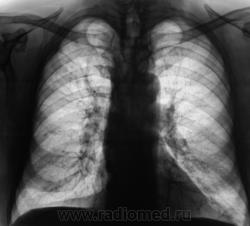

Контроль после флюорографии.

Произведено стандартное дообследование.

Здраствуйте Валентин Львович - не похоже что бы процесс был свежий, а больной без архива?

Процесс свежий. Но, вот кисты справа в верхней доле были, и ранее.